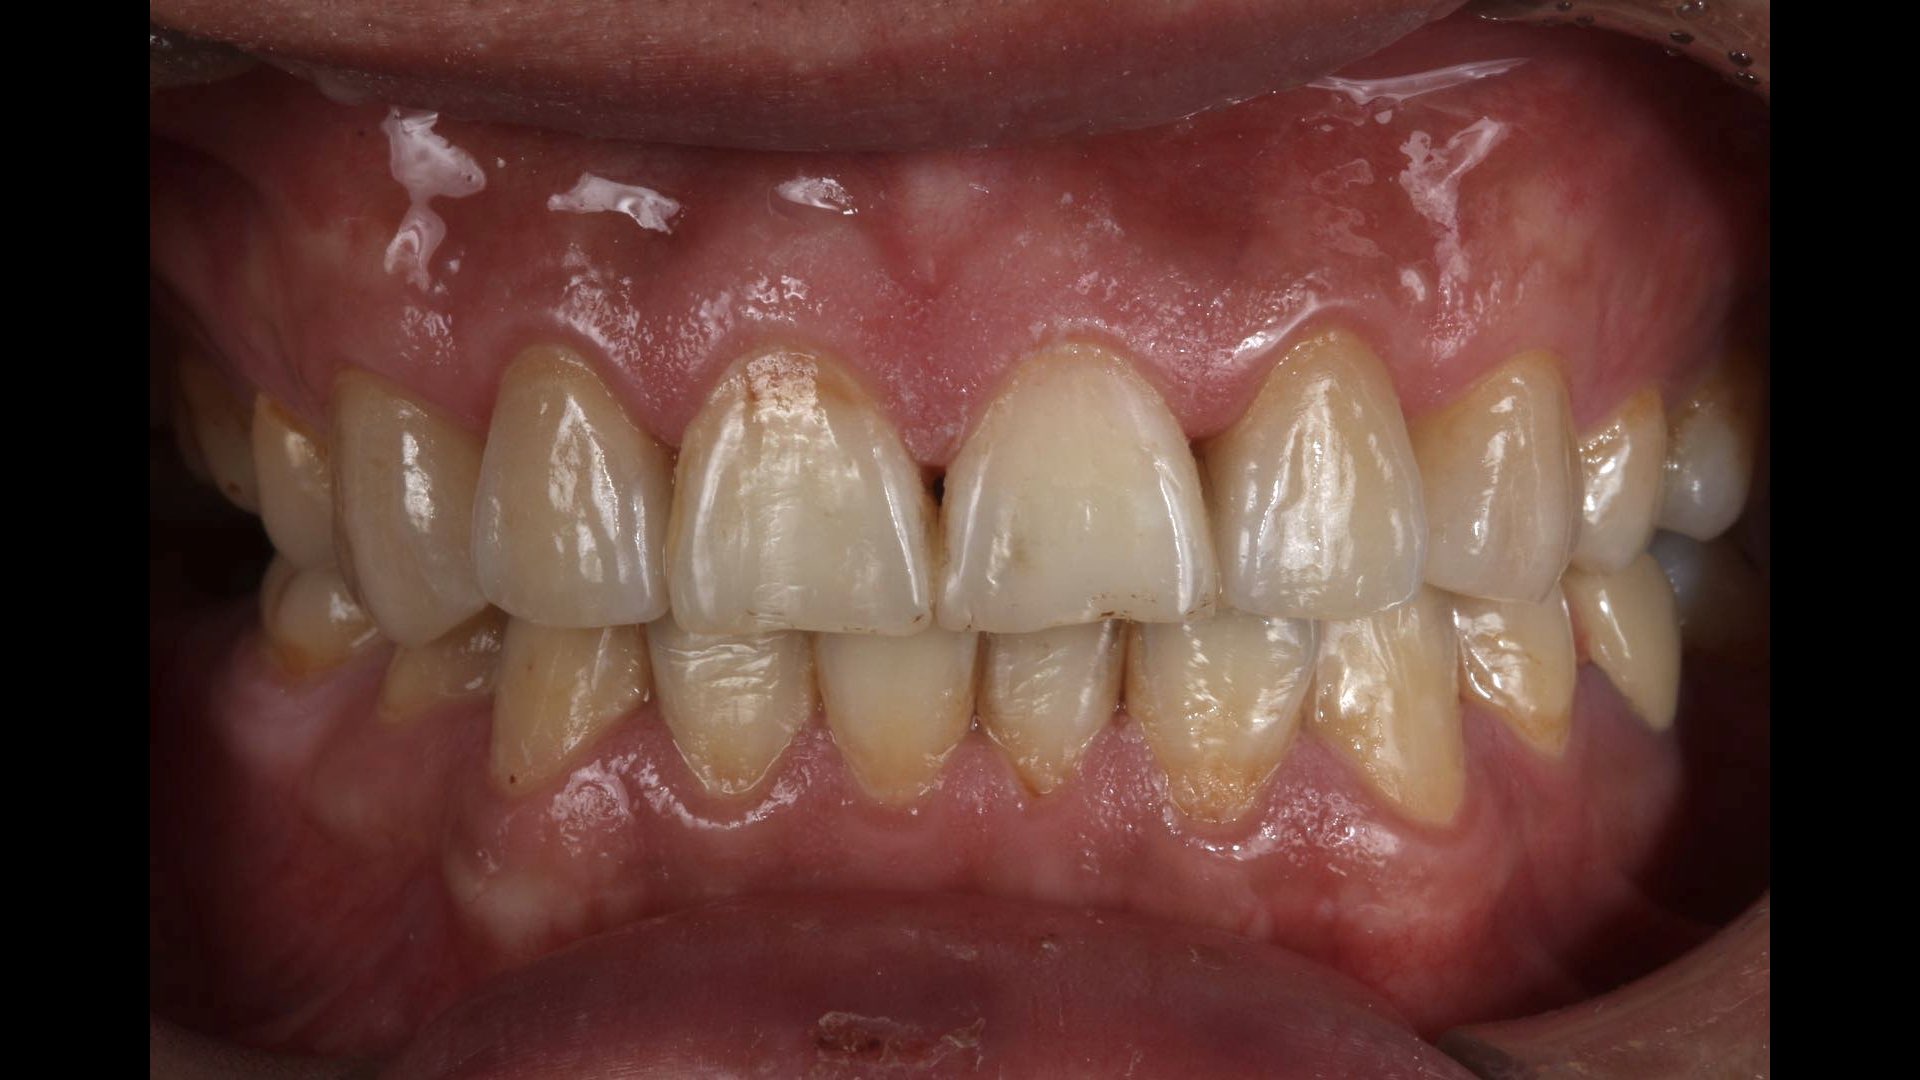

贴面|E.Max .13.12.22.23

温州佳洁口腔 朱照鸿医生 | 技师:贾永青